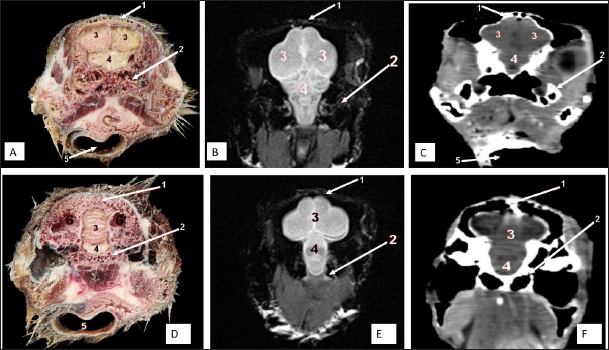

Fig. 2. Sagittal cross section of the adult ostrich head—level 1. A) Photograph of median sagittal anatomical section. B) MRI and C) computed tomography images showing: 1- Os premaxillare, 2- Culmen, 3- Nasal septum, 4- Os nasale, 5- Frontal sinus, 6- Frontal bone, 7- Cranial cavity, 8- Os parietale, 9- Os supraccipitale, 10- Os dentale, 11- Oral cavity, 12- Tongue, 13- Basihyoid, 14- Larynx, 15- Os basisphenoidale, 16- Vomer, and a- Optic lobe, b- Pons, c- Medulla oblongata, d- Cerebral hemisphere, e- Cerebellum, f- Optic chiasma and g- Pituitary gland.

The brain was divided into three parts: the hindbrain (medulla oblongata and cerebellum), the midbrain (cerebrum’s peduncles and optic lobes), and the forebrain (thalamus, pineal body, hypophysis, optic tracts, and chiasm, cerebral hemispheres, and olfactory lobes) (Figs. 2, 9, and 10). The sagittal section of the brain includes the olfactory bulb, cerebrum, cerebellum, medulla oblongata, optic lobe, optic chiasm, and hypophysis (Fig. 2). The dorsal median longitudinal fissure separates the cerebrum into two hemispheres. The sagittal prominence (west) was present on both sides of this fissure (Figs. 9 and 10).

The CT pictures revealed the skull as a readily discernible white structure due to its high CT density, while the brain appeared as a grey structure due to its intermediate density. However, the settings utilized made it impossible to identify different areas of the brain in the CT scans (Figs. 9 and 10C, F). The MRI pictures showed the brain as a whitish structure with a high signal intensity. This technique was used to identify various brain structures, including the hindbrain (medulla oblongata, and cerebellum), the midbrain (peduncles of the cerebrum, optic lobes), and the forebrain (thalamus, pineal body, hypophysis, optic tracts and chiasm, cerebral hemispheres, and olfactory lobes) (Figs. 2B, 9 E, and 10E). Additionally, the olfactory bulb, cerebrum, cerebellum, medulla oblongata, optic lobe, optic chiasm, thalamus, and hypophysis.

The ostrich’s cranial cavity was bounded by frontal bone dorsally, basioccipital and basisphenoid bones ventrally, supraoccipital and parietal bones caudally, interorbital septum rostrally, and temporal bone laterally. The parietal, sphenoid, and temporal bones were pneumatic (Figs. 2, 3, 9, and 10).

Cranium and brain

Two featherless oval nostrils were found on either side of the premaxilla and covered by a characteristic operculum at the entrance. The upper beak’s dorsal ridge (culmen) was located between both nostrils (Fig. 1A and B). The nasal cavity was cone-shaped, extending to reach the choanae. Dorsolateral bony boundaries of the nasal cavity are the frontal process of the premaxilla, nasal, and dorsal horizontal plate of ethmoidal and nasal bone’s lateral process, while the ventral boundary created by the maxillary and palatine processes of the premaxilla, maxilla, and rostral part of the pterygoid and vomer bones. The vomer bone was pneumatic. The nasal septum divides the nasal cavity into two halves and consists of caudal bony and rostral cartilaginous parts (Fig. 2).

Two paranasal sinuses were detected, triangular-shaped infraorbital and two identical frontal sinuses as the infraorbital paranasal sinus was identified as a triangular chamber rostroventral to the orbit (Figs. 3 and 8A), while the frontal paranasal sinuses were positioned dorsally, separating the cranial and nasal cavities. There were two frontal sinuses, one on the right and one on the left, separated by a bone septum in the center. The frontal sinuses were found between the frontal and nasal bones, dorsally and laterally, between the lacrimal and vertical plates of the ethmoidal bone (Figs. 2, 3, 4, 7D, 8, and 9A). All last structures were compared and verified by CT and MRI, to guarantee precise identification and labeling; the anatomical section structures for each cross-section level were matched to their corresponding MRI and CT images. In CT images, the bones appeared white (high CT density), the gaseous parts were black (the lowest attenuation), and the soft tissue was grey (low-to-intermediate CT density). In MR images, bones appeared white (high signal intensity), the gaseous parts were black (no signal intensity), and the soft tissue was grey (low-to-intermediate signal intensity).

The nasal conchae exhibited in the MRI images as bright (high or hyperintense signal intensity) to gray (low or hypointense signal intensity) structures that could be divided into three parts: rostral, middle, and caudal conchae, which correlated to the morphological examinations. In contrast, the nasal conchae could not be recognized clearly on CT images compared to those obtained after MRI (Figs. 25 B and C). The paranasal sinuses with other structures could be identified using both CT and MRI. The nasal septum and paranasal sinuses revealed a white bone border (high signal intensity), soft tissue was grey (low-to-intermediate signal intensity), and they contained black gas, so both the CT and MRI scans showed little signal intensity (Figs. 15B and C and 79B, C, E, F).